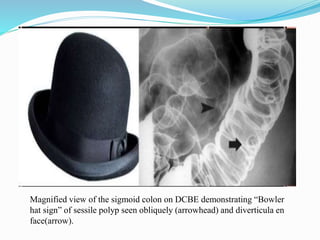

This document discusses colorectal polyps. It defines polyps and describes their types, including neoplastic and non-neoplastic polyps. It discusses adenomatous polyps in depth, noting their malignant potential increases with size over 1cm and villous architecture. Radiological diagnostic methods for polyps including single and double contrast barium enema and CT colonography are explained. The document provides an overview of polyp pathogenesis and genetic syndromes like FAP that increase cancer risk.